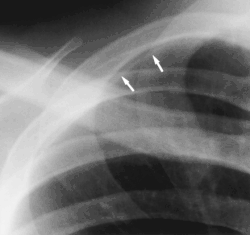

- Clavicular companion shadow is a thin soft-tissue stripe along the upper edge of the clavicle.[1]

Companion shadow is a term used in describing radiographs that denotes the appearance of a smooth, homogenous, radiodensity with a well-defined margin that runs parallel with a bony landmark. Companion shadows represent soft tissue that overlies the respective bony landmark in profile. They are not seen in every radiograph and can be misinterpreted as pathology.